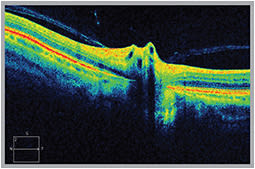

OCT reveals an anomalous posterior vitreous detachment (PVD) leading to vitreopapillary traction syndrome (VPTS).

OCT has improved our ability to understand, diagnose, monitor and incorporate therapy for a wide range of vitreoretinal conditions. OCT provides information about structural changes, and it enables early diagnosis of subtle vitreomacular traction or vitreopapillary traction.